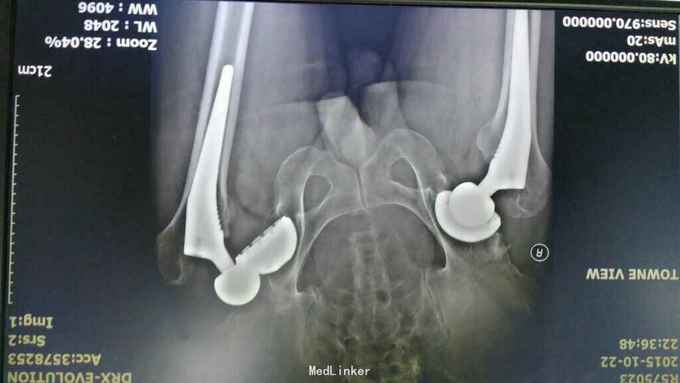

主诉:突发左髋关节疼痛活动受限2小时 病史:2小时前患者吃饭时无明显诱因出现左髋关节疼痛,活动受限,无头晕头痛,无肢体麻木无力,无大小便失禁,患者既往有髋关节脱位史,手扶住髋关节部位就诊。急诊考虑左全髋关节置换术后脱位,为进一步治疗入院治疗。 起病以来,精神可,体力下降,未解大小便。 既往1年前甾院行全髋关节置换术。2月前左髋关节脱位在我院手法复位。

入院查体:平车推入病房,左下肢短缩外旋畸形,左股骨大转子突出,左腹股沟压痛,左大转子叩痛,左足活动感觉正常。左髋关节活动明显受限。 急诊,未行常规检查。 影像学检查结果如下:

诊断:左全髋关节置换术后关节脱位 双侧全髋置换术后 治疗:急诊手法复位

术后复查位置好 考虑左髋臼前倾角度太小?